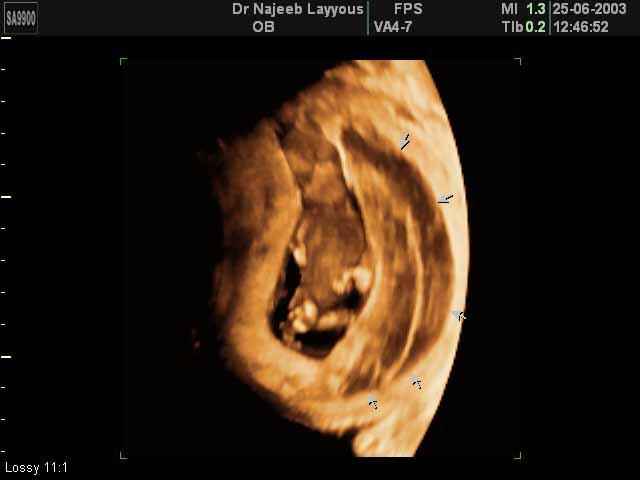

- لقطات فيديو للجنين بجهاز الموجات فوق صوتية رباعي الأبعاد

- صور لوجه الجنين في داخل الرحم

- صور لتصرفات الجنين داخل الرحم